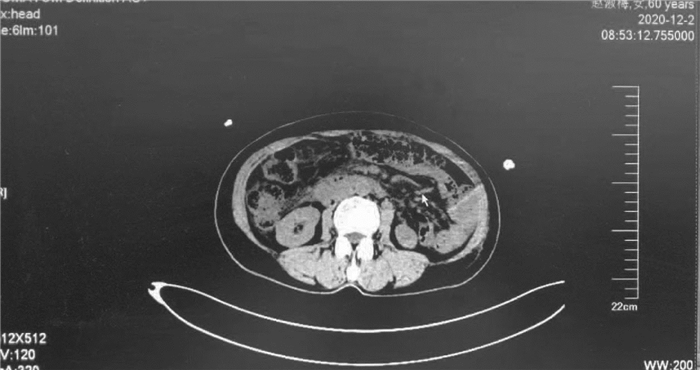

A case of acute cerebral infarction with splenic rupture secondary to splenic infarction

Qin YU, Chen CHEN, Qian XIA, Jin CHEN

2021, 37(10): 2417-2419. DOI: 10.3969/j.issn.1001-5256.2021.10.033

Abstract(973) HTML (292) PDF (2433KB)(58)

Abstract: